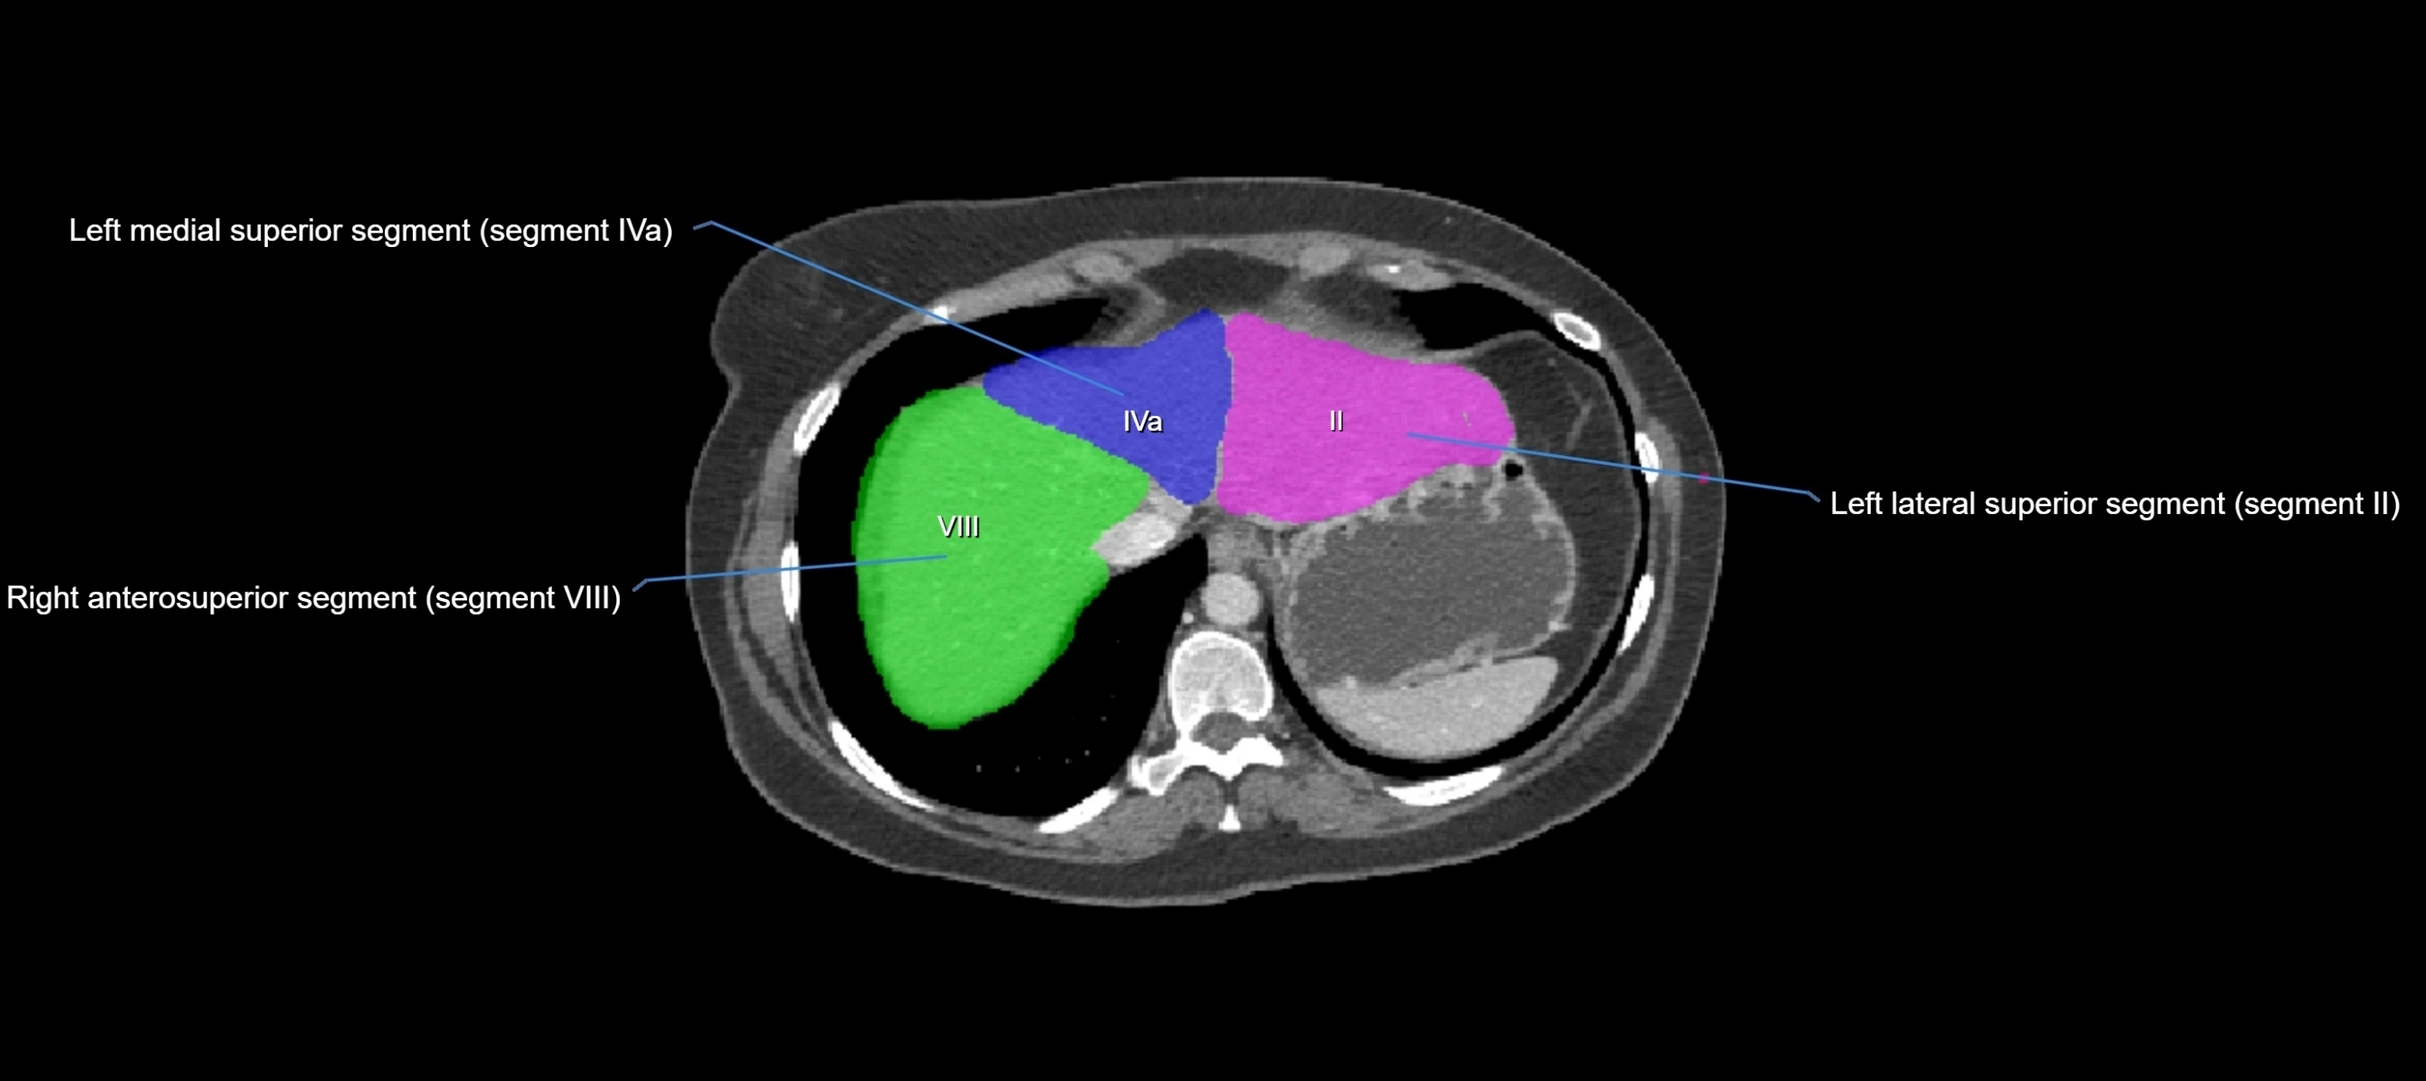

CT Appearance

CT Pre-Contrast:

• Caudate lobe appears as a soft-tissue density, isodense to the rest of the liver

• Enlargement may be appreciated in cirrhosis or Budd–Chiari syndrome

CT Post-Contrast:

• Homogeneous enhancement in the portal venous phase, similar to rest of liver

• Independent venous drainage into the IVC may be visualized

• Lesions follow characteristic CT enhancement patterns (HCC: arterial hyperenhancement with washout; hemangiomas: peripheral nodular enhancement with centripetal fill-in)

CT Venous Phase (functional significance):

• Caudate lobe often enhances relatively more than other lobes in Budd–Chiari syndrome, due to preserved venous outflow

CT Image

image